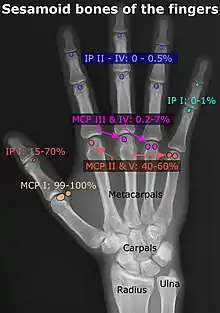

- In the hand—two sesamoid bones are commonly found in the distal portions of the first metacarpal bone (within the tendons of adductor pollicis and flexor pollicis brevis). There is also commonly a sesamoid bone in distal portions of the second metacarpal bone.

- Chen W, Cheng J, Sun R, Zhang Z, Zhu Y, Ipaktchi K, et al. (2015). "Prevalence and variation of sesamoid bones in the hand: a multi-center radiographic study". Int J Clin Exp Med. 8 (7): 11721–11726. PMC 4565393. PMID 26380010.